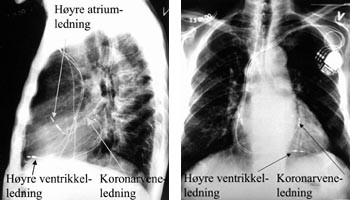

Terskelen for stimulering må kontrolleres også etter at introduserhylsen er fjernet og ledningen er fiksert, fordi ledningen lett kan dras ut av posisjon pga. den kraftige medstrømmen som er i sinus coronarius når man skal fjerne den 45 cm lange innføringshylsen. Deretter innføres en standard bipolar pacemakerledning via introduser i v. cephalica til apeks av høyre ventrikkel. Dersom pasienten har sinusrytme, innføres også en standard bipolar atriepacemakerledning via ny introduser i v. cephalica til høyre atriumsaurikkel (fig 2). Etter at høyre ventrikkel-ledningen er plassert, avledes elektrogrammet fra høyre ventrikkel og epikardialt fra venstre ventrikkel via pacemakerelektroden i kornarvenen simultant både på EKG-skriver og med pacingsystemanalysator (Medtronic analyzer 8090TM). Med skriverhastighet 100 mm/s måler man den interventrikulære ledningstiden ut fra elektrogrammene fra høyre ventrikkel og fra venstre ventrikkel (fig 3). Det bør være lengst mulig spredning i tid mellom ventriklenes spontane aktiveringselektrogrammer for at man ved pacing skal få best mulig resynkronisering av høyre og venstre ventrikkel. Tersklene for stimulering, P-bølgeamplituden og R-bølgeamplituden måles i henholdsvis høyre aurikkel og høyre ventrikkel med pacingsystemanalysator. Til slutt kobles alle ledningene til pulsgeneratoren InSyncTM som plasseres i pacemakerlommen.

Pasient 3 er en 76 år gammel mann med postinfarkt hjertesvikt (tab 1, 2). EKG viste sinusrytme og venstre grenblokk med QRS-bredde 180 ms (tab 3). Det ble implantert atriobiventrikulær pacemaker etter den angitte metoden (tab 3, 5, fig 2). Allerede første postoperative døgn angav pasienten at dette var første natten på lang tid han ikke våknet av dyspné.